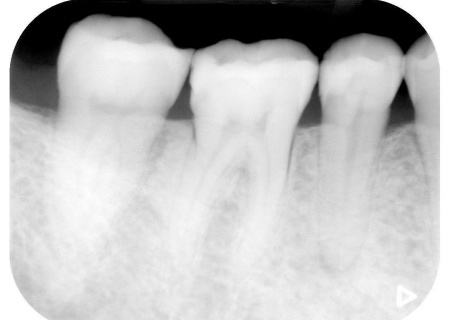

・詰め物や被せ物による治療

右上の歯には、見た目が自然で耐久性の高いセラミック素材「e-max」を用いて、アンレー(歯の一部を覆う詰め物)による治療を行います。

詰め物が合っていない左上奥歯2本は、強度に優れたセラミック素材「ジルコニア」を用いた修復を計画しました。

・歯を削る量を最小限に抑える治療

前歯部は歯の温存を優先し、虫歯を除去したあとに白い詰め物「CR(コンポジットレジン)」で修復します。

右下奥歯3本と左下奥歯2本については、虫歯を除去したあとに歯科用樹脂を直接歯に盛り付けて形を整える「ダイレクトボンディング」を行います。